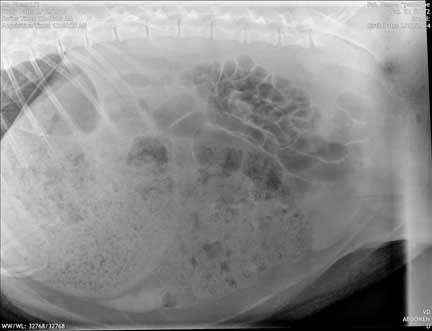

Before we show the surgery photos let’s have some fun and show you a radiograph of a pig abdomen. This pot-bellied pig is lying on its right side, with the head to the left. It is a picture of the abdomen. Almost everything you see in this radiograph is the intestines. They have a very long intestinal tract, a fact that will become obvious when you see the surgery pictures.

This is typical for a pot-bellied pig